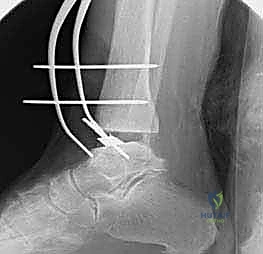

4. وضع أدلة القطع (Jig Placement and Alignment)

تعتمد دقة الجراحة على المحاذاة الصحيحة. يتم استخدام أجهزة توجيه متطورة (Jigs) تثبت على عظمة الساق باستخدام دبابيس معدنية. يتم التحقق من صحة الزوايا والمحاور باستخدام جهاز الأشعة السينية المباشر داخل غرفة العمليات (C-arm Fluoroscopy). يضمن الدكتور هطيف أن يكون القطع موازياً للأرض تماماً عند وقوف المريض.